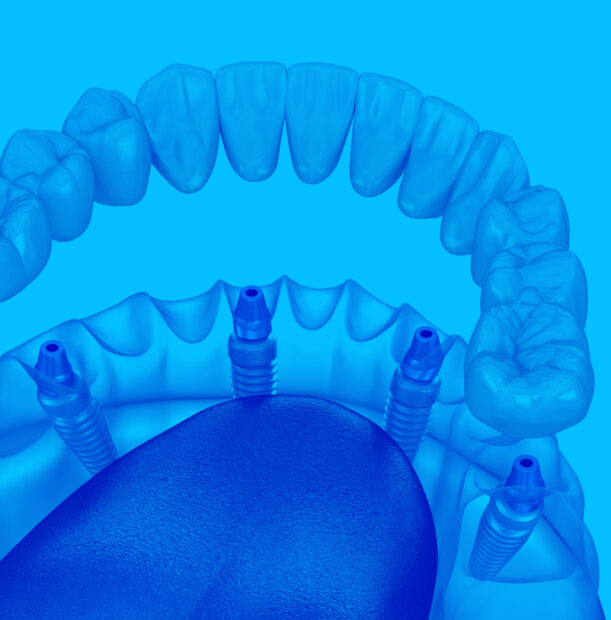

Что такое имплантация

All-on-4

Что такое имплантация

All-on-4

Протез устанавливается не на опорные зубы (которых при полной адентии и нет), а на предварительно вживленные 4 импланта. Импланты устанавливаются в кость челюсти в заранее определенные участки, и затем на имплантах фиксируется зубной протез

Имплант имеет сложное строение, включающее три базовых элемента:

Установка имплантов

4 импланта с одномоментным удалением больных зубов

Мультиюнит абатменты

Оригинальные абатменты для винтовой фиксации протеза

Слепочные трансферы

Для точного позиционирования будущих зубов при создании оттиска